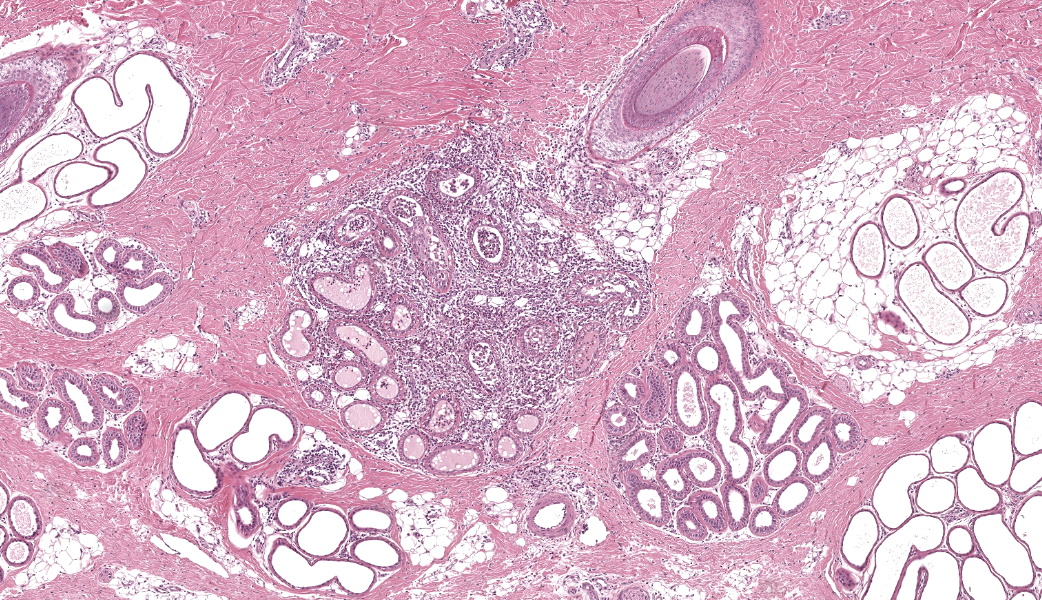

Haired skin (dorsal nose, three sections): Within the deep dermis and subcutis there are multiple well delineated clusters of variably distended apocrine glands with sinuous cystic cavities and partial tubular folding, which expand and replace dermal adipose tissue and muscle . Most of the clustered cysts are lined by a single layer of flattened columnar epithelial cells without apical blebbing. Adjacent smaller clusters of lesser distended glands exhibit one to several layers of more cuboidal epithelium. The outer layer of the cyst wall consists of thin layers of myoepithelial cells. Many gland lumina contain pale eosinophilic secretory product. Surrounding tissue and stroma comprises mild lymphoplasmacytic infiltrates.Focally in the mid dermis and associated with a hair follicle there is a localized, well demarcated focus of moderate mixed cellular inflammation composed of macrophages, neutrophils and lesser lymphocytes and plasma cells. These encase numerous distorted and/or ruptured apocrine glands, infiltrate their epithelium and are present within the lumen of remaining glandular structures (foreign body type reaction). Macrophages frequently contain cellular debris.

Skin: cystic distention of apocrine glands, diffuse, severe, with compression of adjacent muscle tissue consistent with cutaneous apocrine cystomatosis.Skin: hidradenitis and dermatitis, focally extensive, moderate, chronic, mixed cellular with apocrine gland rupture (foreign body type reaction).

There was brief discussion on the inflammatory component in this case. Mild inflammation of apocrine glands, known as hidradenitis, is a common background lesion in many species that is usually associated with folliculitis. In this case, the focus of inflammation was severe enough that it was unanimously thought by conference participants to be due to a ruptured apocrine gland secondary to dilation. There was a question posed to participants regarding possible other differentials based on gross images in other species, and included apocrine cystadenoma, basal cell adenoma, sebaceous adenoma, or melanocytic neoplasms. Of these, apocrine cystadenoma vs. apocrine cystomatosis was discussed most heavily for educational purposes, the main differences being that this lesion was diffuse throughout the skin, which is more common with cystomatosis, and there are no papillary projections into the lumens of affected glands. Papillary projections of epithelial cells into the cystic glandular lumen are a common finding in apocrine cystadenomas, but not in cystomatosis.7 Wrapping up conference discussion of this case was a brief review of apocrine cystomatosis lesions in other species, which are discussed by the contributor in their comment.